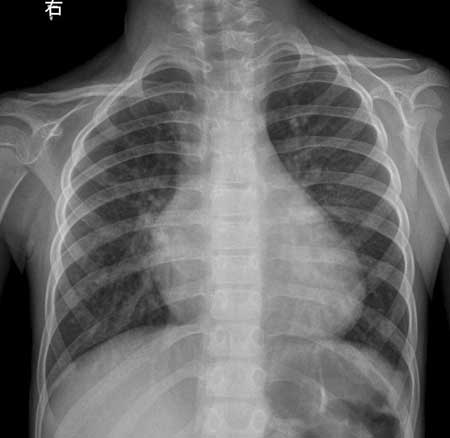

以下是引用听蝉观竹在2007-2-12 1:22:00的发言:[br]1、肺血增多-----提示有血液左向右分流;常见有房缺、室缺、动脉导管未闭。[br]2、肺动脉段突出,心尖圆隆,右前斜位肺动脉圆锥隆起------右心室增大,而左心室不增大;室缺、动脉导管未闭虽然可以右心室增大、肺动脉段突出,但同时左心室也增大,符合者就剩下房缺了。[br]3、手术前右前斜位吞钡食道压迹加深,正位片右心缘第二弓明显增大-----有心房增大。手术后右心缘第二弓正常,说明右房压力正常。[br]4、主动脉结明显缩小-----这是房缺的特征表现。[br][br]虽然没有告诉心脏杂音的性质位置,根据影像分析-------房间隔缺损。重要的一点:房缺在透视下肺门“舞蹈”明显,比其它左向右分流先心更显著。[br][br][本贴已被 听蝉观竹 于 2007-2-12 1:34:56 修改过]